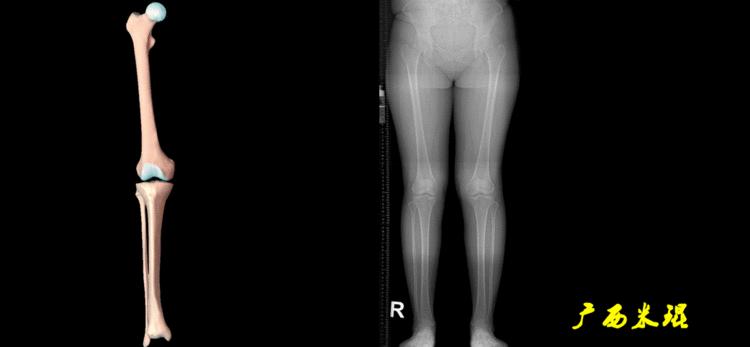

(2)机械轴

机械轴是连接近端和远端关节中心点的直线。

机械轴要分前后位及侧位,站立前后位(也就是冠状面)股骨头中心与踝关节中心的连线通过膝关节中心,这是下肢的机械轴线,也就是下肢力线,常说Mikulicz线。冠状面的力线评估在临床工作中最常用、最基础、最重要。

最常见的下肢畸形发生于冠状面,即膝内外翻畸形,冠状面的对线异常通过应用“对线异常检验”进行分析,机械轴的偏移(MAD)表现为对线异常。

膝内翻是指下肢力线通过膝关节中心点内侧,距中点2mm以上,偏内超过15mm为显著膝内翻。膝外翻是指下肢力线通过膝关节中心点外侧,距中点2mm以上,偏外超过10mm为显著膝外翻。